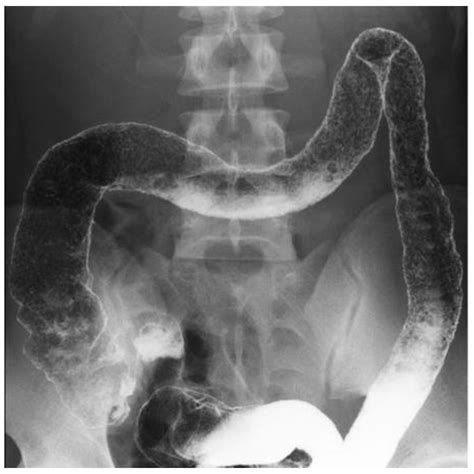

• Barium Enema: A diagnostic test where a contrast dye is inserted into the colon to highlight any irregularities during an X-ray.